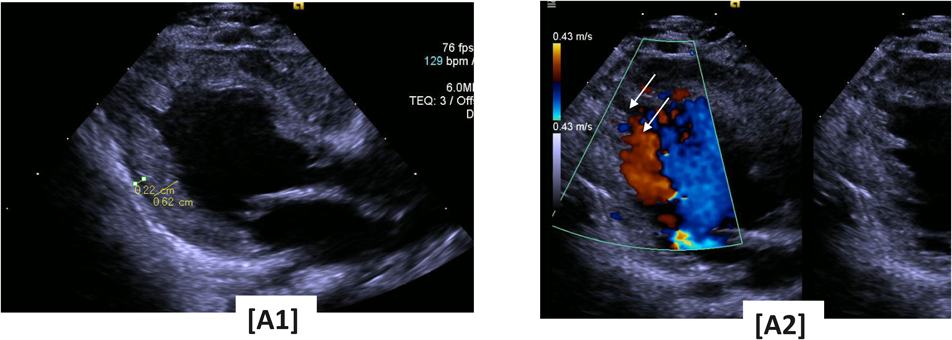

The infant’s clinical course is shown in Table 1 and Fig. 3. We initially treated the patient with diuretics and carvedilol, which alleviated the HF. However, over time, the HF progressed and could not be adequately controlled. An ACE inhibitor (enalapril: initial dose, 0.05 mg/kg/day; target dose, 0.2 mg/kg/day) and calcium sensitizer (pimobendan, 0.03 mg/kg/day) were added to his regimen. By 8 months of age, the patient’s condition had stabilized, and he exhibited normal cognitive development. However, by 9 months of age, his cardiothoracic ratio gradually increased; his LVDs, LVDd, LVESV, LVEDV, and LV E/e had increased; his LVEF had decreased; and mitral valve regurgitation gradually developed. In the 2DST echocardiography analysis, his endocardial, transmural, and epicardial GCS at the middle levels were decreased to −8.1%, −4.6%, and −3.0, respectively, as compared with the data at 2 months of age. The HF showed clinical signs of progression. Moreover, retrospective analysis of cardiac rotation revealed normal heart rotation, counterclockwise rotation of the cardiac base, and clockwise rotation of the cardiac apex. His cardiac rotation indicated that the cardiac base and apex had rotated in the counterclockwise direction, the so-called reverse apical rotation (RAR), with abnormal rotation of the cardiac apex in the same direction (Fig. 2 (B1), (B3)). At 12 months of age, the infant died due to progressive HF induced by dilated cardiomyopathy (DCM) with LVNC. At postmortem, he was diagnosed with BTHS with LVNC and neutropenia. However, we could not confirm the growth delay and skeletal myopathy and did not examine urinary excretion for 3-methylglutaconic acid. Informed consent was obtained as inclusion agreements based on the “Japanese Ethical Guidelines for Medical and Health Research Involving Human Subjects.”

Fig. 3 Clinical course

We initially treated patients with diuretic agents and carvedilol, which alleviated the heart failure. By 8 months of age, the patient’s condition had stabilized and he exhibited normal cognitive development. However, at 9 months, his cardiothoracic ratio gradually increased; his LVDs, LVDd, LVESV, LVEDV, and LV E/e had increased; his LVEF had decreased; and mitral valve regurgitation gradually developed. However, the dilated cardiomyopathy could not be controlled with carvedilol alone; hence, pimobendan and enalapril were additionally administered. After 8 months of age, his left ventricular diastolic dimension, left ventricular systolic dimension z-score, and B-type natriuretic peptide level had gradually increased. At 12 months of age, he died of progressive heart failure induced by dilated cardiomyopathy with LVNC. Abbreviations: BNP, B-type natriuretic peptide; CDI, color Doppler images; LVDd, left ventricular diastolic dimension; LVDs, left ventricular systolic dimension; LVEF, left ventricular ejection fraction; MR, mitral valve regurgitation.